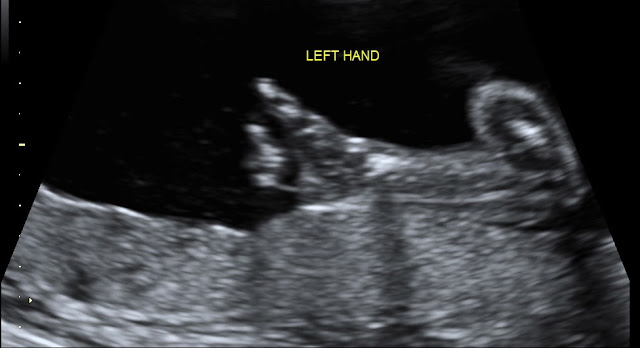

Best moment this week: Seeing baby at our 20-week anatomy scan. What an amazing experience. Seeing baby's heart and brain and spine and kidneys was surreal. We actually saw all for chambers of the heart and the blood flowing through it...it was incredible. I am thrilled to report that baby looks healthy and was moving a ton during the u/s. Baby weighed 13 oz and was in the 75th percentile for size. Oh, and the tech confirmed that baby is still a girl. I wanted them to check again to get the green light to buy some girl clothes. Here are a few shots from our a/s:

Baby giving the "thumbs up"